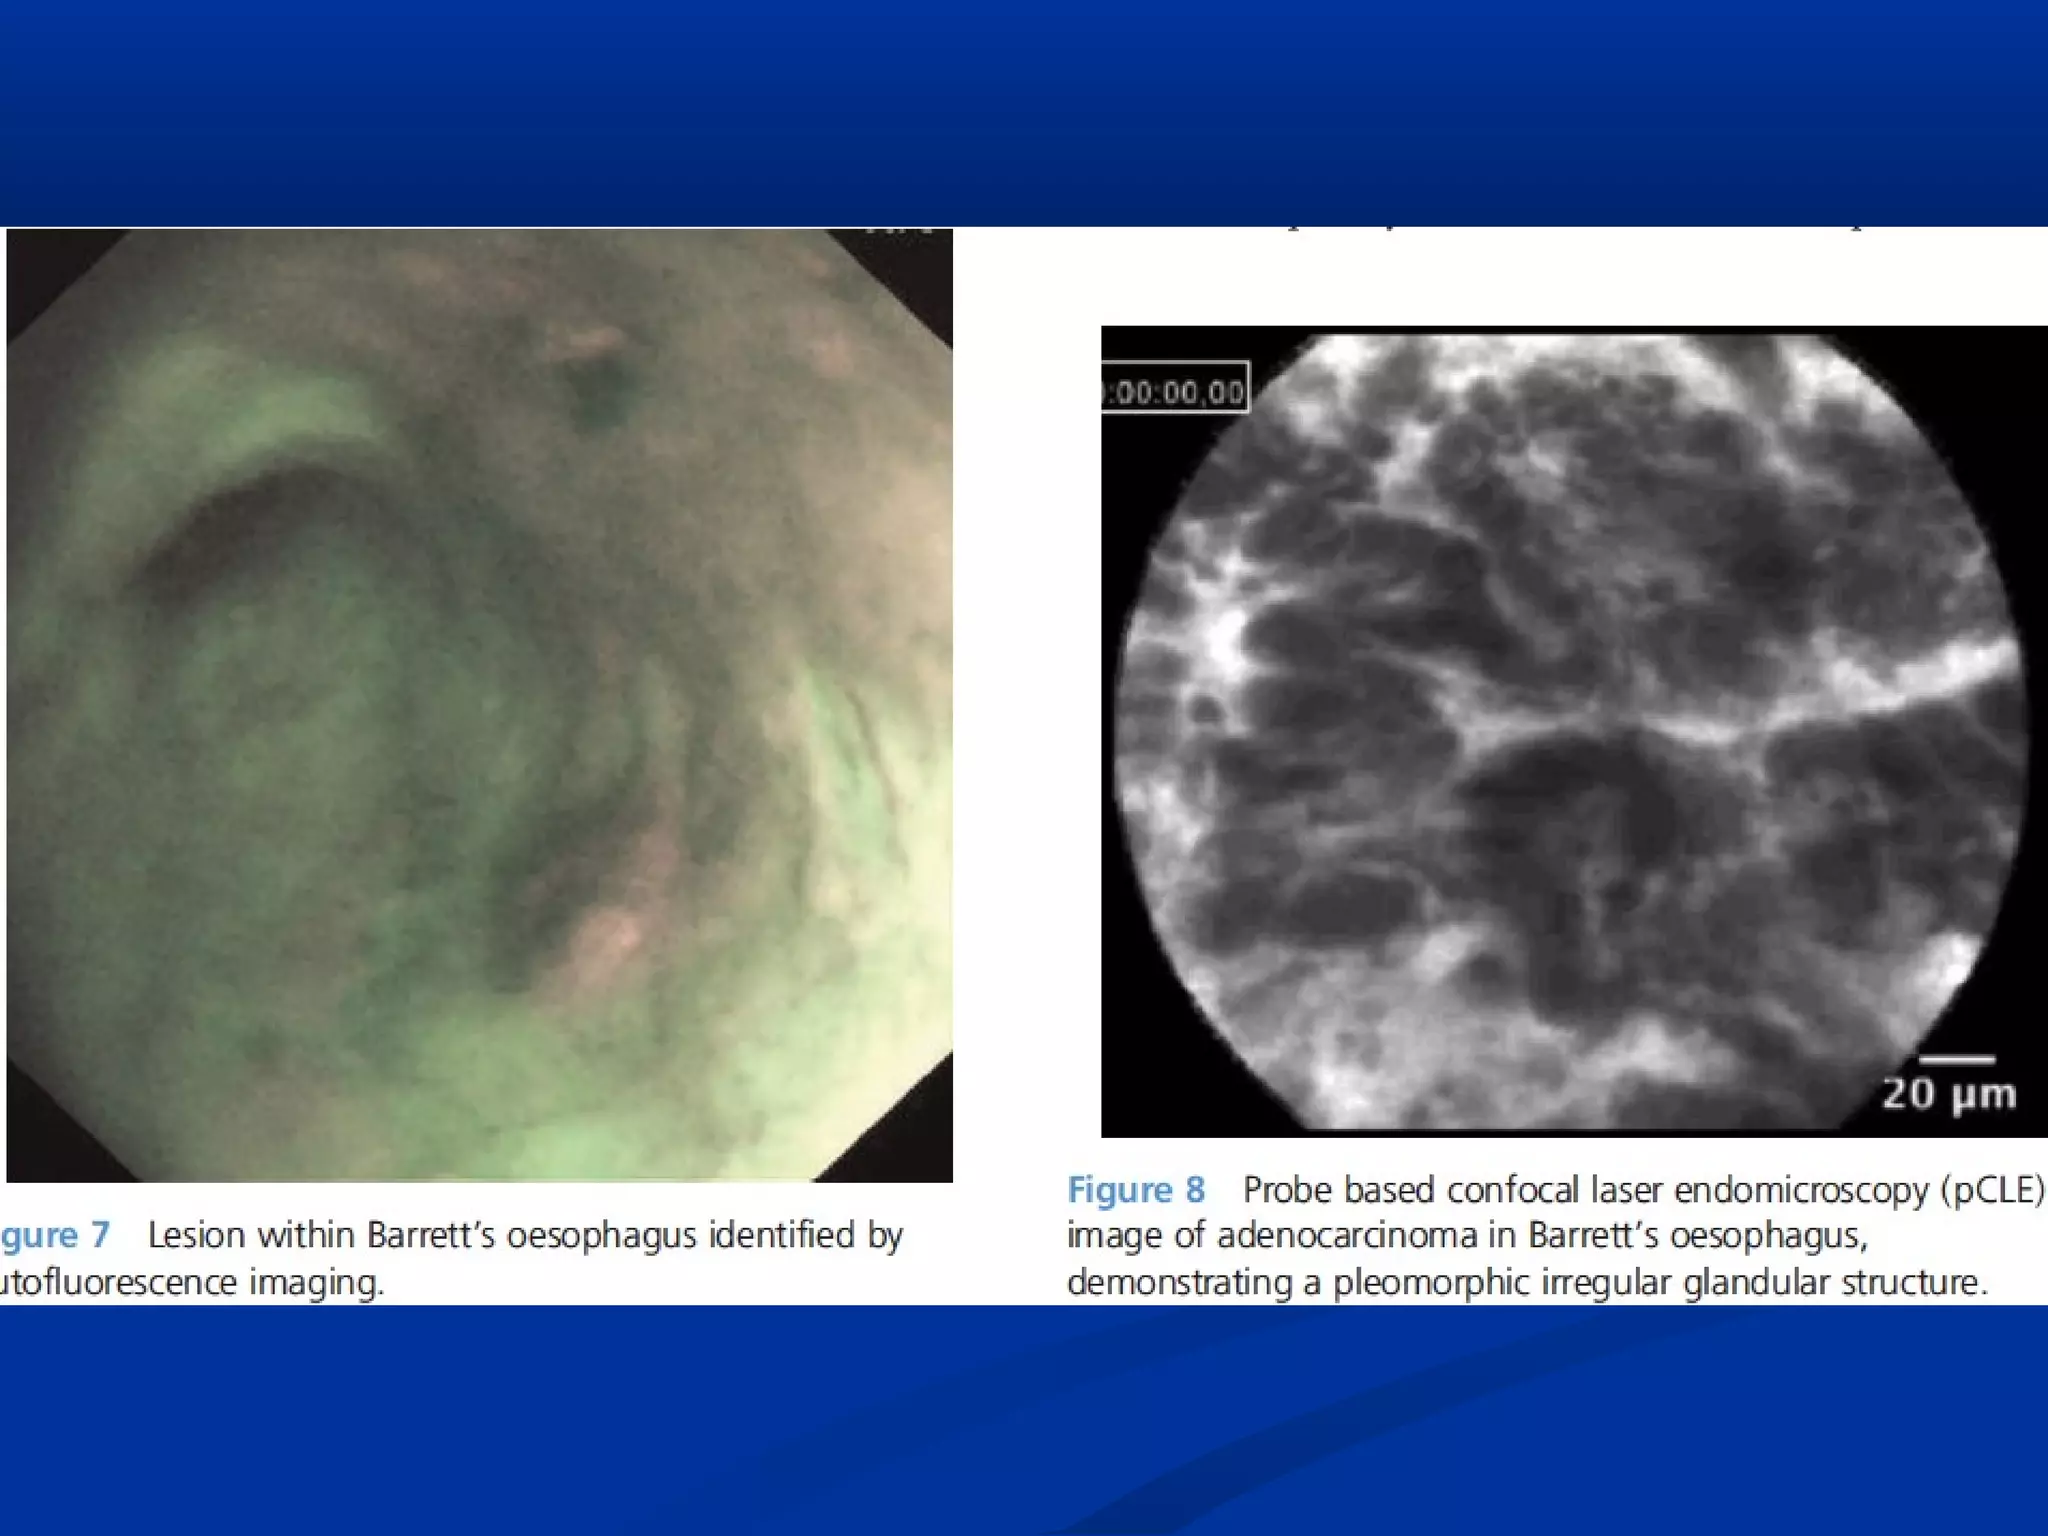

Types: AFITypes: AFI

 Autofluorescence imaging (AFI) takes advantage of the differentialAutofluorescence imaging (AFI) takes advantage of the differential

presence of naturally occurring endogenous fluorophores withinpresence of naturally occurring endogenous fluorophores within

the GI mucosa.the GI mucosa.

 This results in an image composed of a mixture of green/mauveThis results in an image composed of a mixture of green/mauve

hues, which represent areas of normal/dysplastic mucosa,hues, which represent areas of normal/dysplastic mucosa,

respectivelyrespectively

Types: CLETypes: CLE

 AFI has shown initial promising results in increasing dysplasiaAFI has shown initial promising results in increasing dysplasia

detection but unfortunately is associated with a high false positivedetection but unfortunately is associated with a high false positive

rate, which can be as high as 80% so incorporated with NBI & HDrate, which can be as high as 80% so incorporated with NBI & HD

WLE to create endoscopic trimodal imaging (ETMI).WLE to create endoscopic trimodal imaging (ETMI).

 The use of AFI is currently limited to expert endoscopists in high-The use of AFI is currently limited to expert endoscopists in high-

riskrisk patients.patients.